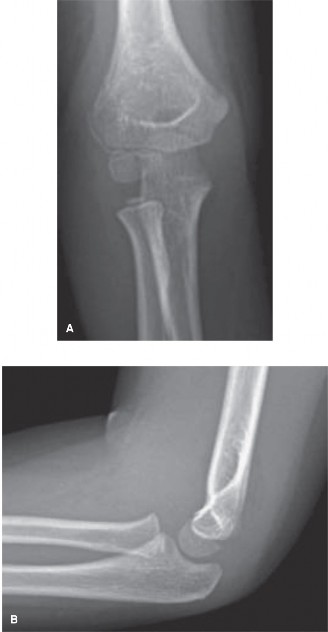

CASE 4 An 11-year-old girl was transferred from an outside hospital for furthe…